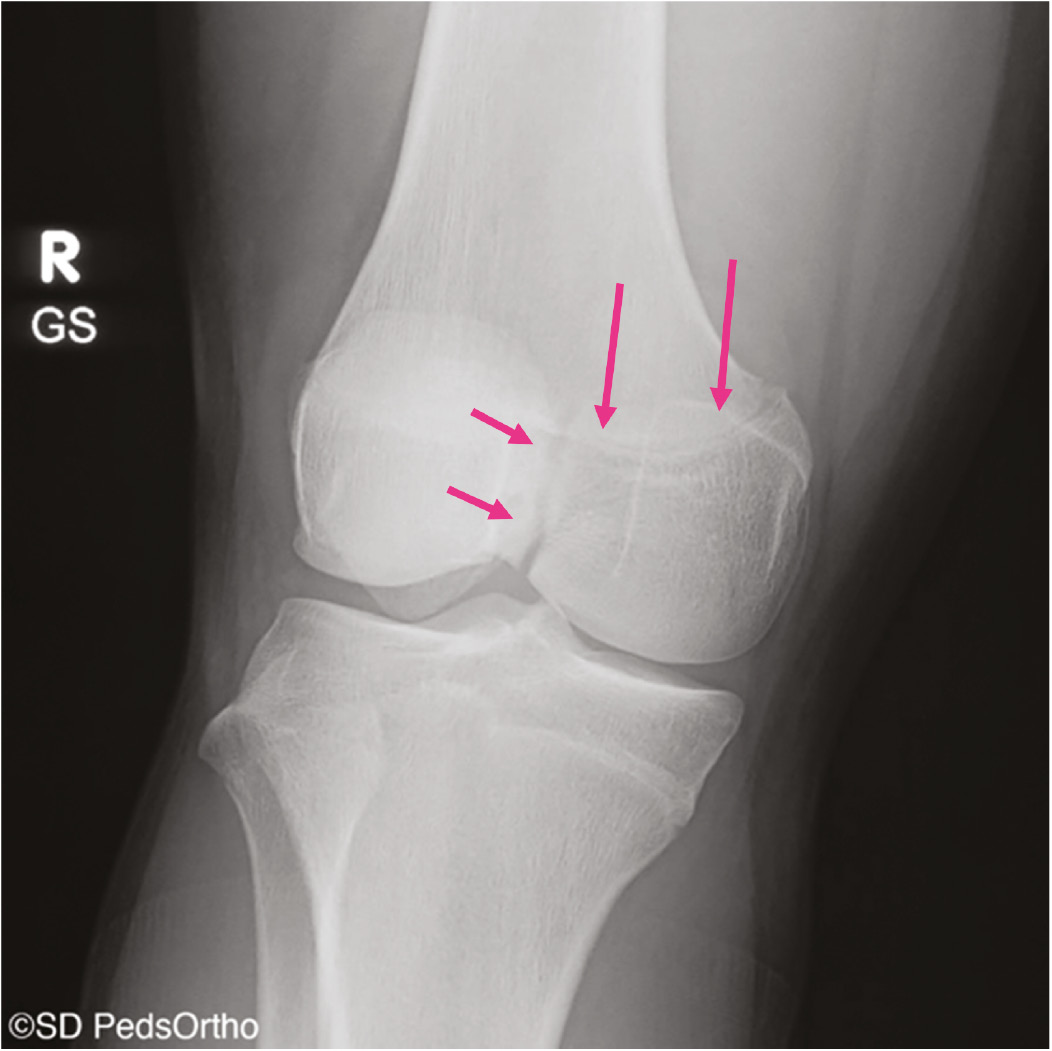

At a minimum, two radiographs (AP/lateral views) of the knee should be obtained, but a four-view series (AP/lateral/merchant/tunnel views) may be preferable to minimize the chance of missing other pathology. Examples would be a Salter-Harris III fracture of the medial femoral condyle, which represents a transitional fracture that is seen in adolescents near skeletal maturity as an alternative to an adult MCL injury (Figure 2). Additional injuries to the MCL complex include medial epicondyle fractures or fractures to the most prominent aspect of the medial condyle, bony avulsions of the deep MCL, which are frequently associated with ACL tears (Figure 3), or even the rare Salter-Harris I or II fracture of the proximal tibia in which the MCL can become interposed within the fracture (Figure 4). With longer-term follow-up, periosteal avulsions of the MCL adjacent to the medial epicondyle may result in the formation of a Pellegrini-Stieda lesion where ossification of the proximal MCL is present from either a previous avulsion of the MCL or ossification within the MCL from a chronic tear/injury pattern (Figure 5). In cases of chronic instability with suspected genu valgum, a long leg alignment film is helpful in quantifying any underlying coronal plane malalignment that may need to be corrected simultaneously or prior to a ligamentous reconstruction.

Figure 2. 15-year-old male football player with a Salter-Harris III fracture of the medial femoral condyle (pink arrows).